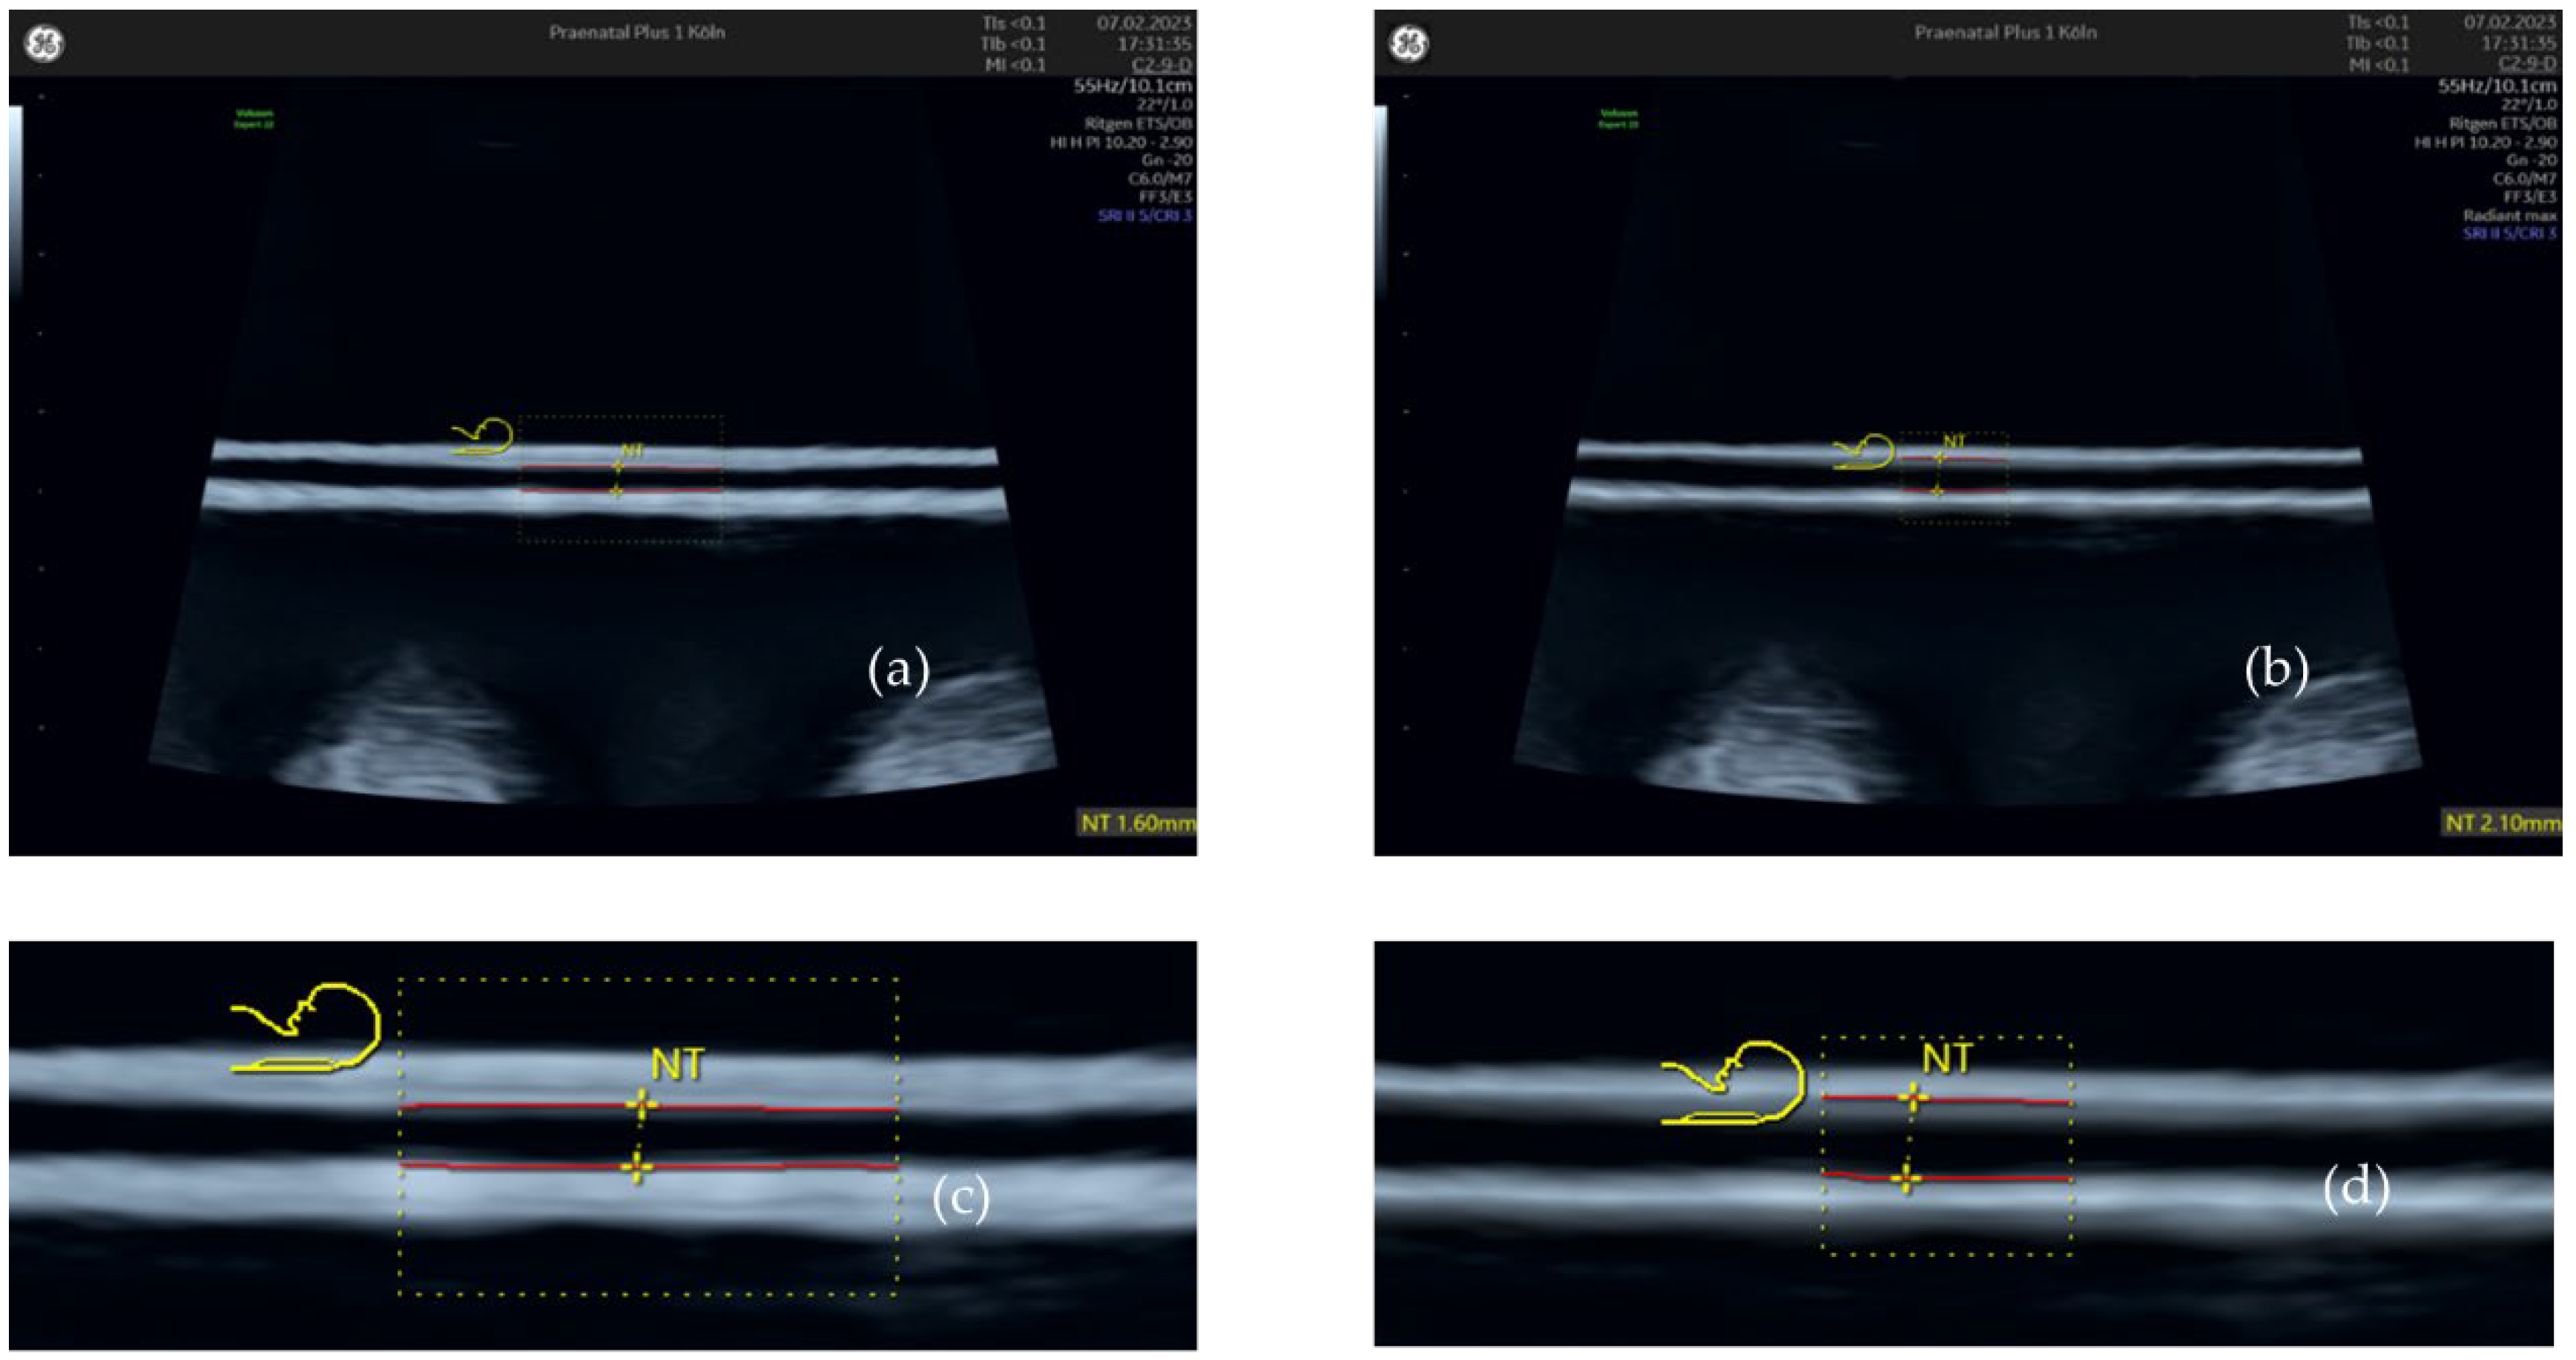

2.1. Nuchal Translucency with and without ‘Radiant’ Applied

3.1. Nuchal Translucency with and without ‘Radiant’ Applied

| vs. ‘Radiant min’ | 0.19 mm | 0.17 – 0.21 | 0.010 | p < 0.001 |

| vs. ‘Radiant mid’ | 0.24 mm | 0.22 – 0.27 | 0.012 | p < 0.001 |

| vs. ‘Radiant max’ | 0.30 mm | 0.27 – 0.33 | 0.016 | p < 0.001 |